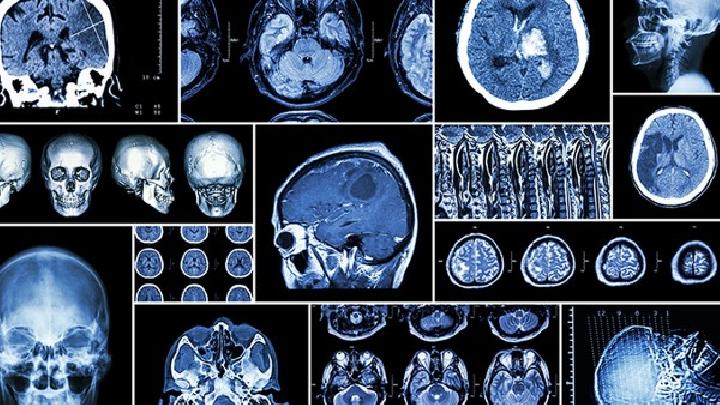

如今,越来越多的儿童患有先天性脑积水,发病率也越来越高,给许多家庭带来了巨大的经济负担。脑积水是一种非常严重的疾病,脑积水会出现脑过大等现象,严重的水会导致儿童死亡的严重危害,一旦发现脑积水应积极治疗。

50%先天性脑积水患儿在2~5岁期间自然缓解,称为静止性脑积水,无需治疗。50%症状逐渐恶化称为进行性脑积水,头部明显增大,大脑皮层厚度超过1cm者,可采取手术治疗,手术可分为以下几种: